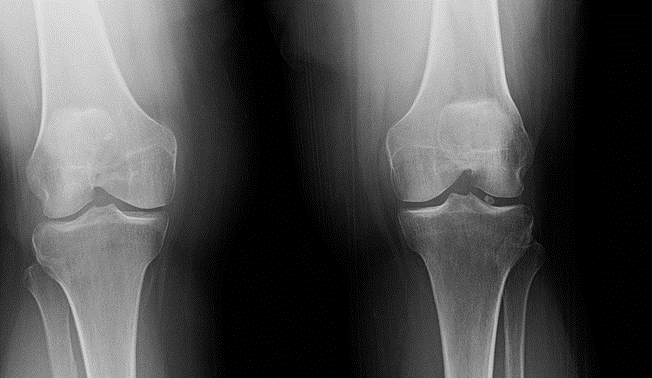

Loose bodies in the knee joint may get may be diagnosed via plain radiographs (x-rays) taken at the doctor’s office. To get a more detailed look, a CT or MRI may be performed, with or without dye injected to better visualize the loose body if needed (an x-ray of the knee after a dye has been injected is called an Arthrography). Sometimes these are seen incidentally during a knee arthroscopy (surgical scope of the knee).